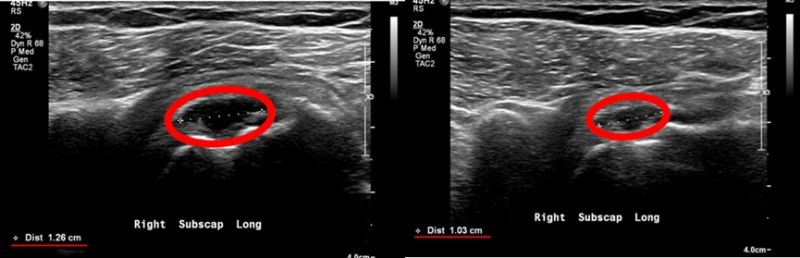

若肌腱撕裂傷口大於兩公分,醫師通常會考慮轉介至骨科進行縫合手術;但若撕裂約一公分,除了傳統的物理治療與復健外,也可以透過注射治療來修復軟組織。舉例來說,曾經有位68歲的阿嬤在照顧孫子時不慎被輕微拉扯,隨即感到右肩劇烈疼痛,並伴隨上臂無力。經新光醫院復健科陳文玲主任理學檢查及超音波檢查後,發現她的肩膀旋轉袖肌腱撕裂達1.26公分,而非手術最快治療的方式,為注射專利軟組織修復劑。在陳文玲主任的超音波導引下注射下,阿嬤接受完整的兩劑療程後,其症狀改善,且超音波影像顯示原本的肌腱破裂處已縮小。

肩旋轉肌破裂之損傷可藉由超音波影像診斷(圖片提供:新光醫院復健科陳文玲主任)